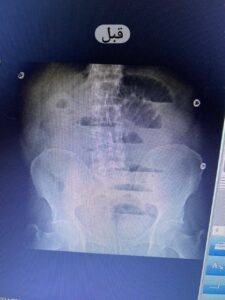

تبين بالكشف الطبي وجود فتق إربي أيسر مختنق وتم إجراء أشعة تليفزيونية وأشعة عادية على البطن أظهرت وجود انسداد معوي.